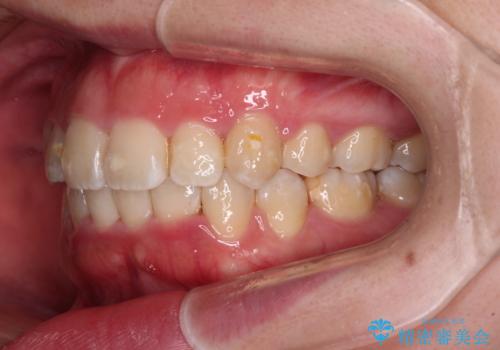

- 上下の八重歯やデコボコを気にして来院された患者様です。

上下ともに八重歯が顕著であったので、上下左右第一小臼歯4本を抜歯し、補助装置を使用して速やかに改善しながら、ワイヤー装置にて矯正治療を行うこととしました。

気になっていた八重歯は装置装着から3か月ほどで解消されました。

2年以内を目標として治療を開始しましたが、1年半ほどで終えることができました。